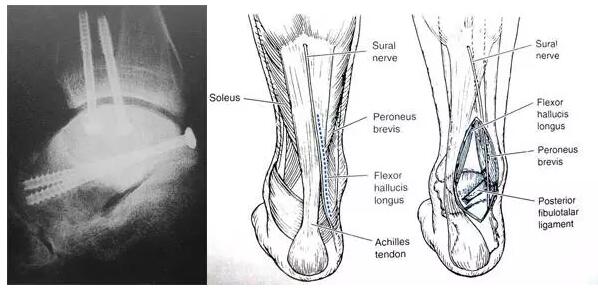

4后外侧入路

长屈肌腱和腓骨肌肌腱间显露

后外侧入路的固定